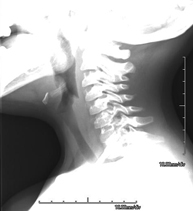

- RX Columna cervical

Tècnica que usa els raigs X a través de la qual s'obtenen imatges de la columna cervical per al seu estudi. Indicacions: traumatisme, contractura cervical, dolor articular. - RX Ossos propis nasals

Tècnica que usa els raigs X a través de la qual s'obtenen imatges de la columna cervical per al seu estudi. Indicacions: traumatisme, dolor cervical. - RX Columna dorsal